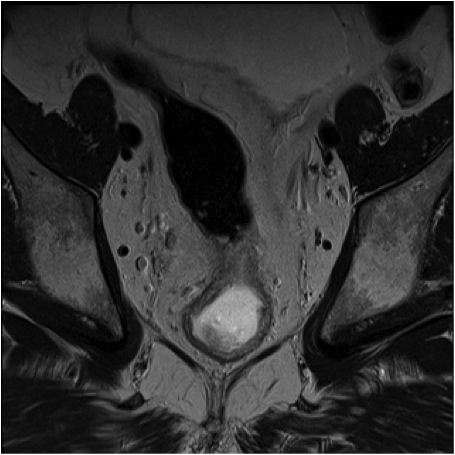

Fig.2. Același pacient post chimio-/ radioterapie – răspuns complet cu dispariția masei tumorale rectale; dispariția restricției de difuzie și reducere în dimensiuni a ganglionilor mezorectali; pacientul a beneficiat de TME şi s-a confirmat histopatologic absenţa ţesutului tumoral (pT0 pN0).

a-d) imagini T2 ponderate în 3 planuri

e) difuzie RM (b1000)

f) sagital T1 postcontrast